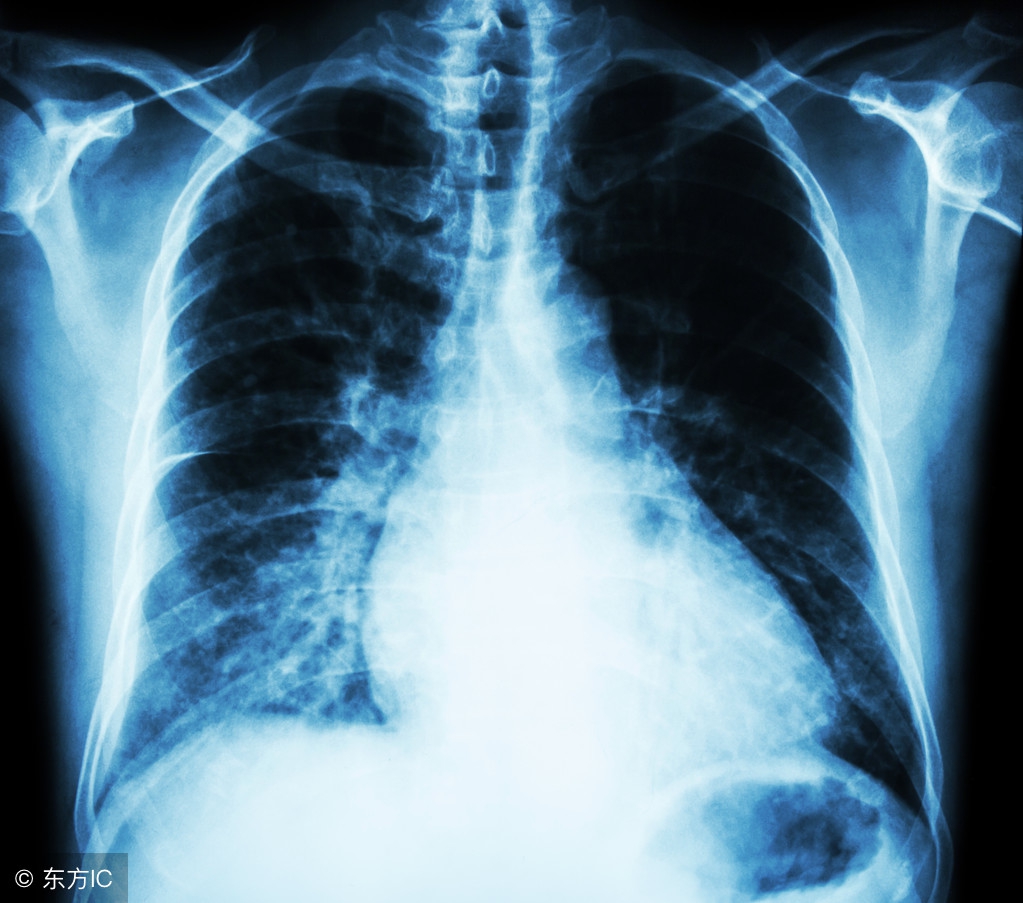

体检:45岁以上要做低剂量CT

《2017中国肿瘤登记年报》的统计显示,中国肺癌发病率、死亡率双率第一。定期体检非常重要,尤其是40岁以上人群,每年做一个低剂量CT,能够帮助发现早期肺癌,而手术治疗早期肺癌预后非常好,大多数不需要化疗。